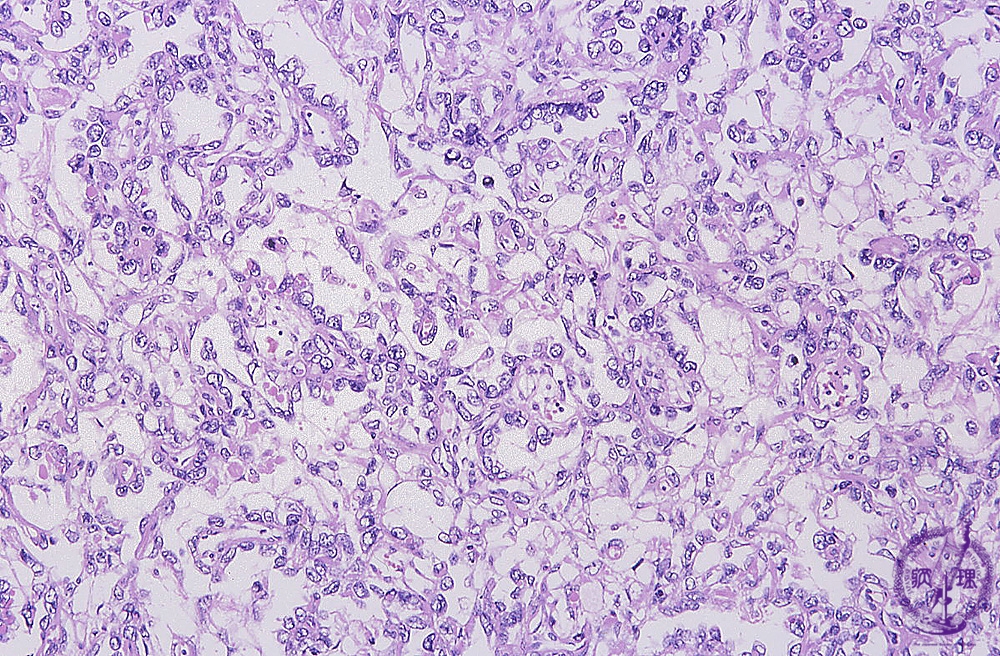

Histology (HE stain, intermediate power): Yolk sac tumor with endodermal sinus pattern. Tumor cells proliferates in net-like pattern.